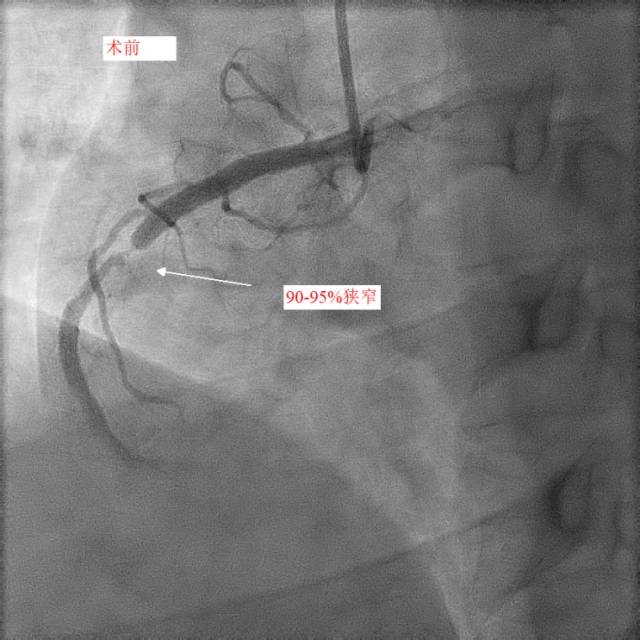

第二天,小天和父亲同一天接受冠脉造影和手术治疗,冠脉造影进一步明确了:小天冠状动脉回旋支完全堵死、前降支90%堵塞,而右冠状动脉也仅有一丝血流通过。造影中医生发现,小天的血管狭窄已经有一段时间,其中的右冠状动脉已经产生了侧支循环。随后医生在患者右冠状动脉里放入了两个支架,恢复了血流。

康慧元医生说:“患者的三条心脏血管都严重堵塞,很容易发生急性心梗甚至猝死,手术先开通慢性堵塞的右冠状动脉,保证心脏有足够的血流。”